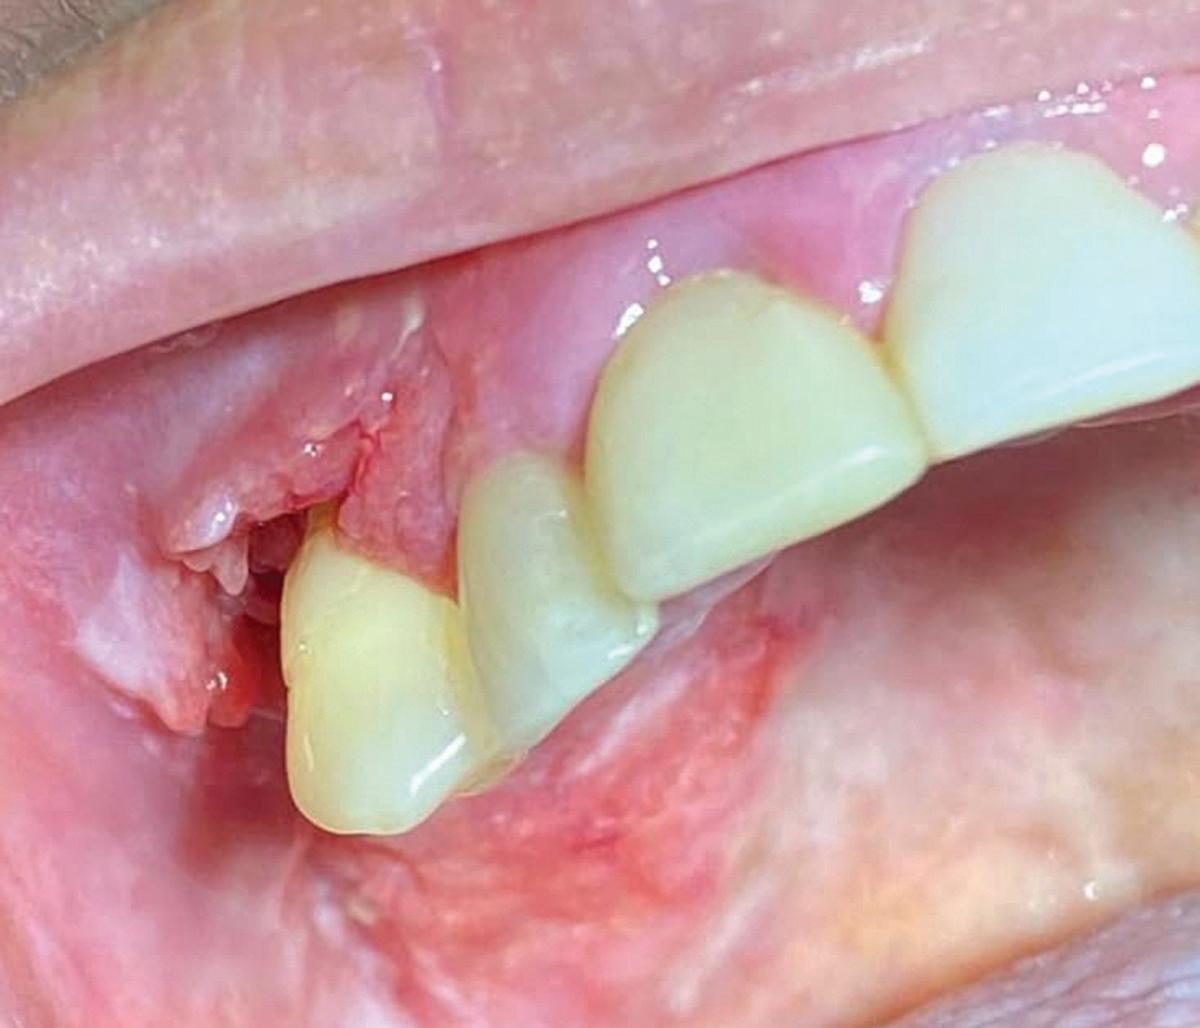

Tooth replacement from extraction to restoration. 3. Second-stage and impression procedures

The third part of this series reviews uncovering of implants that were buried in a 2-stage approach, provisionalization of the implant, and impression and scanning techniques.1 These techniques are all crucial for the final restorative outcome of the implant. The uncovering and second-stage procedures set the foundation for the shape and position of the soft tissue, which are very important esthetic factors. This information must also be properly transferred to the laboratory via a highly accurate impression so the laboratory has as much information as possible. If these steps are done properly, the result will be implant crowns that are easy to seat, biologically ideal, and esthetically pleasing.